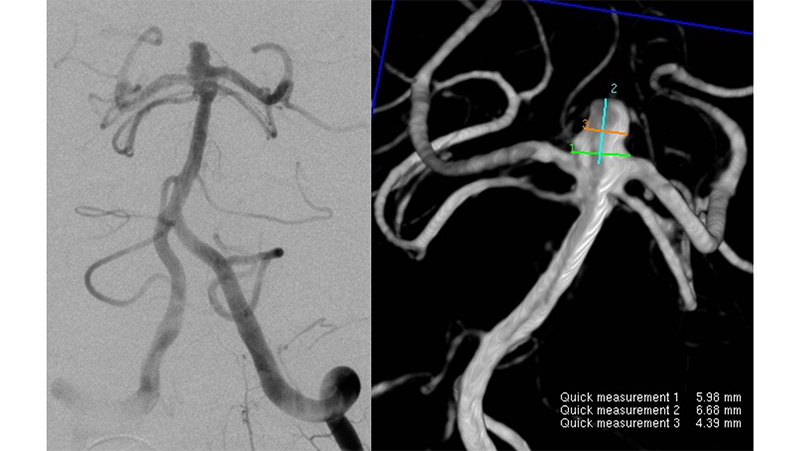

Εικόνα 3: Όπως φαίνεται το εύρος του αυχένα είναι 6 χιλιοστά.